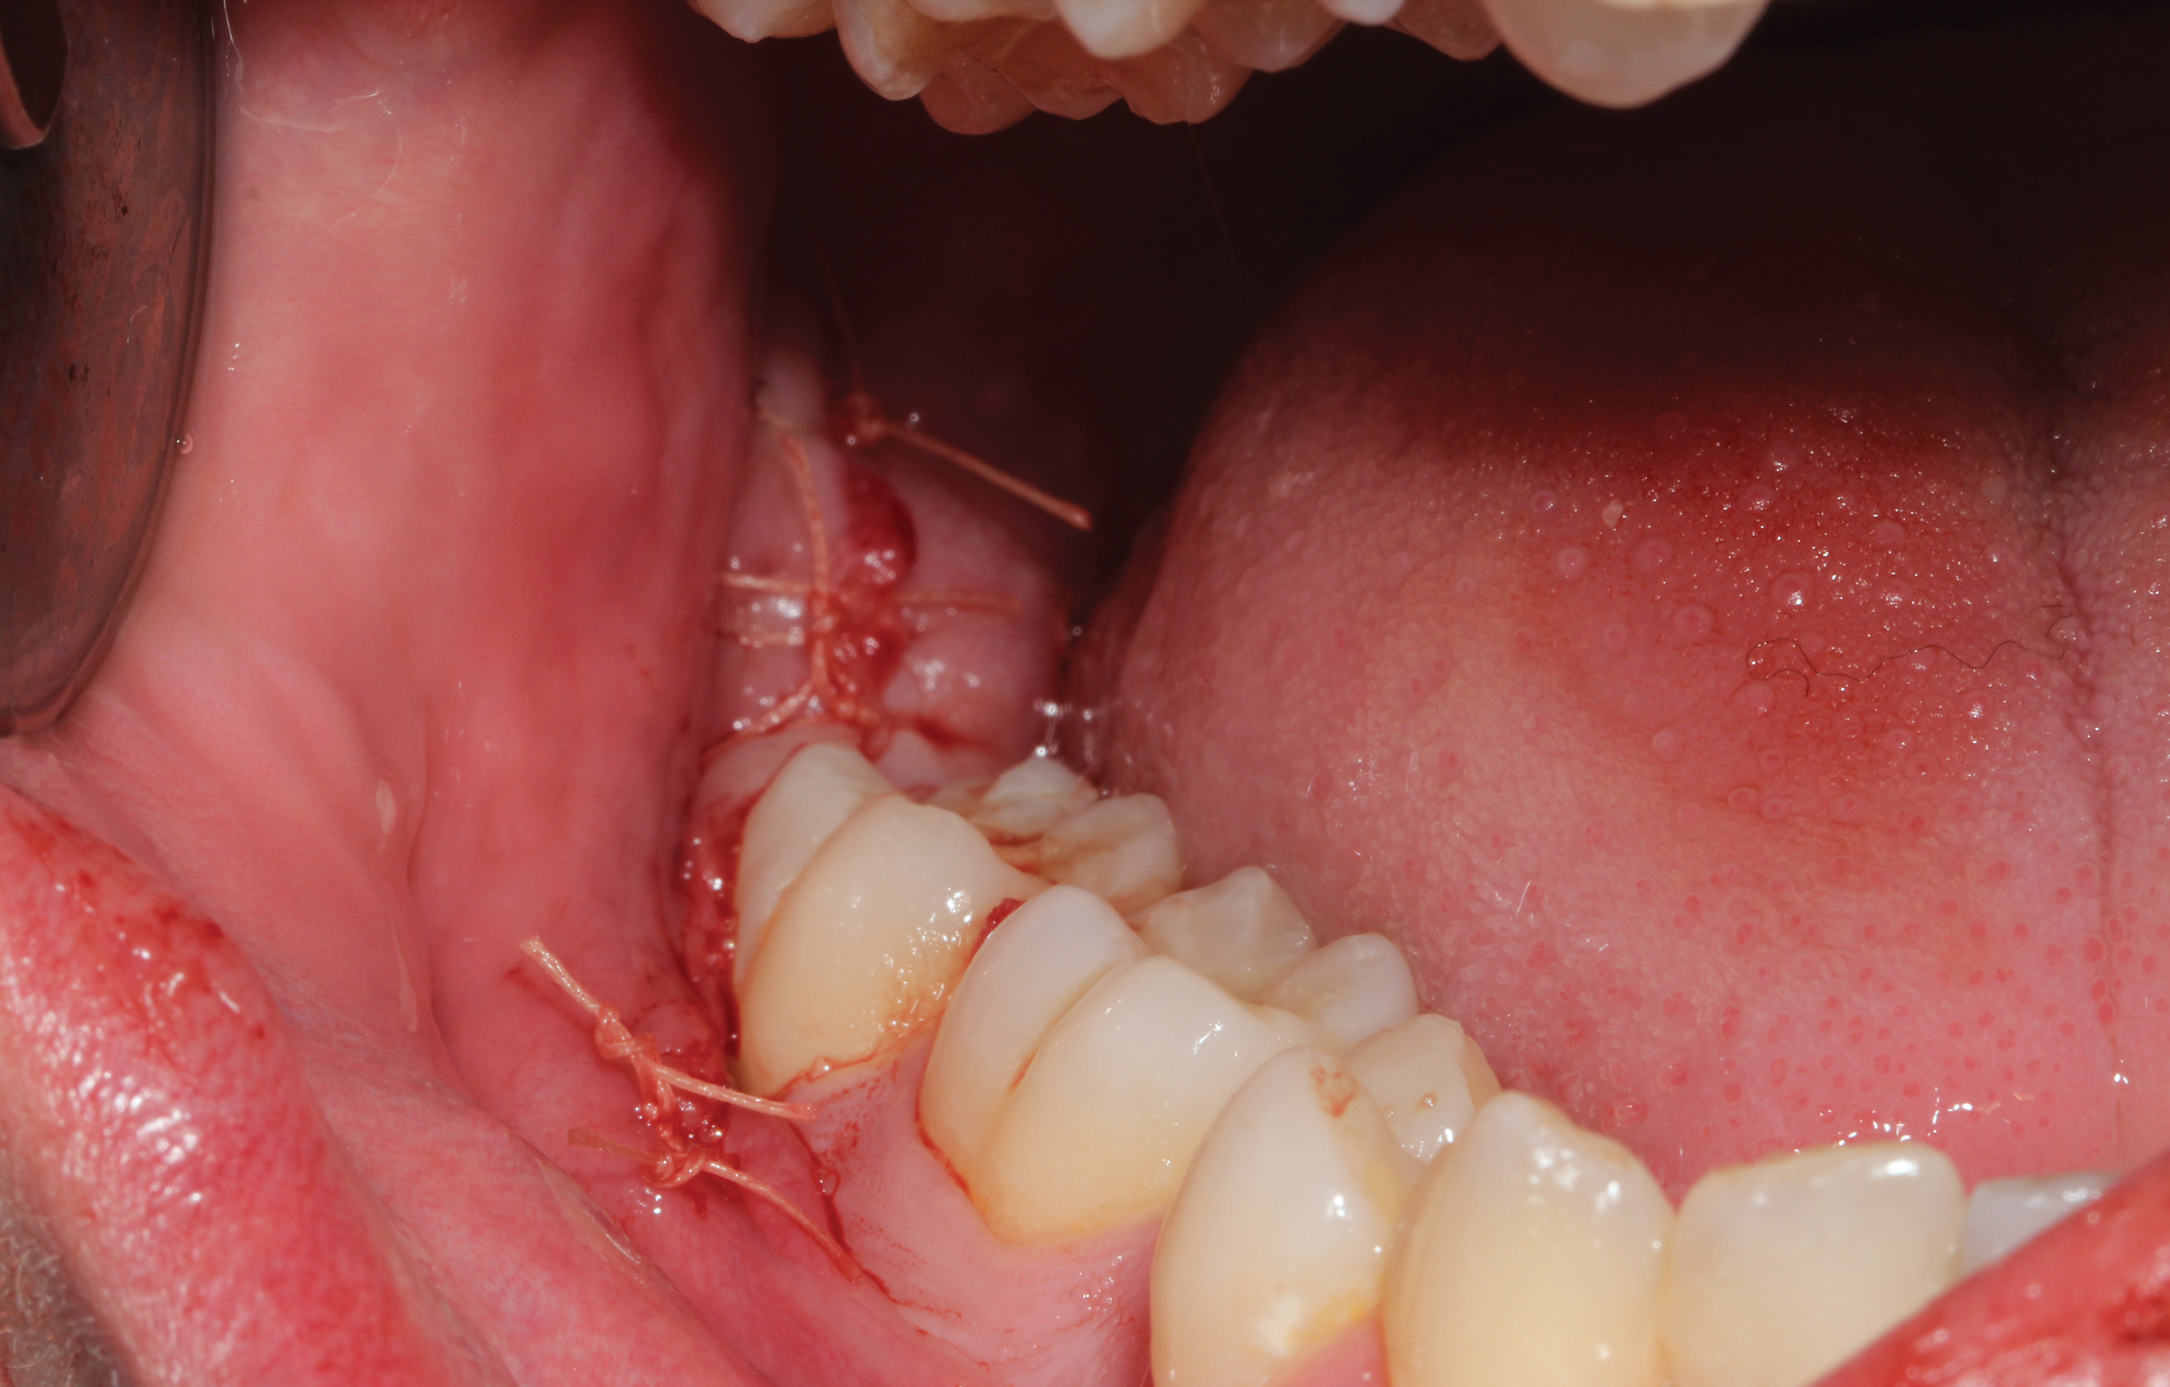

A presurgical rinse of 0.2% chlorhexidine (CHX) solution was performed, followed by administration of local anesthetic using 4% articaine with epinephrine solution. A crestal incision with a vertical releasing incision at the mesial aspect of the surgical area was made, and a full-thickness mucoperiosteal flap was elevated (Figure 1). A buccal and, if required, distal osteotomy was performed using a round carbide bur on a straight handpiece. When necessary the tooth was dissected to allow it to be elevated and extracted (Figure 2). When performing the third molar extraction care was taken to not damage the adjacent second molar tooth nor its supporting alveolar bone. The extraction socket was thoroughly debrided with hand instruments and rinsed with a 0.2% CHX solution to decrease bacteria in the socket (Figure 3).35

Fig 1. Impacted mandibular third molar showing mesial angular orientation after flap elevation to expose the tooth in preparation for extraction.

Figure 1

Fig 7. Flap was repositioned to achieve primary closure, and 4-0 vicryl sutures were placed to secure the flap.

Figure 7